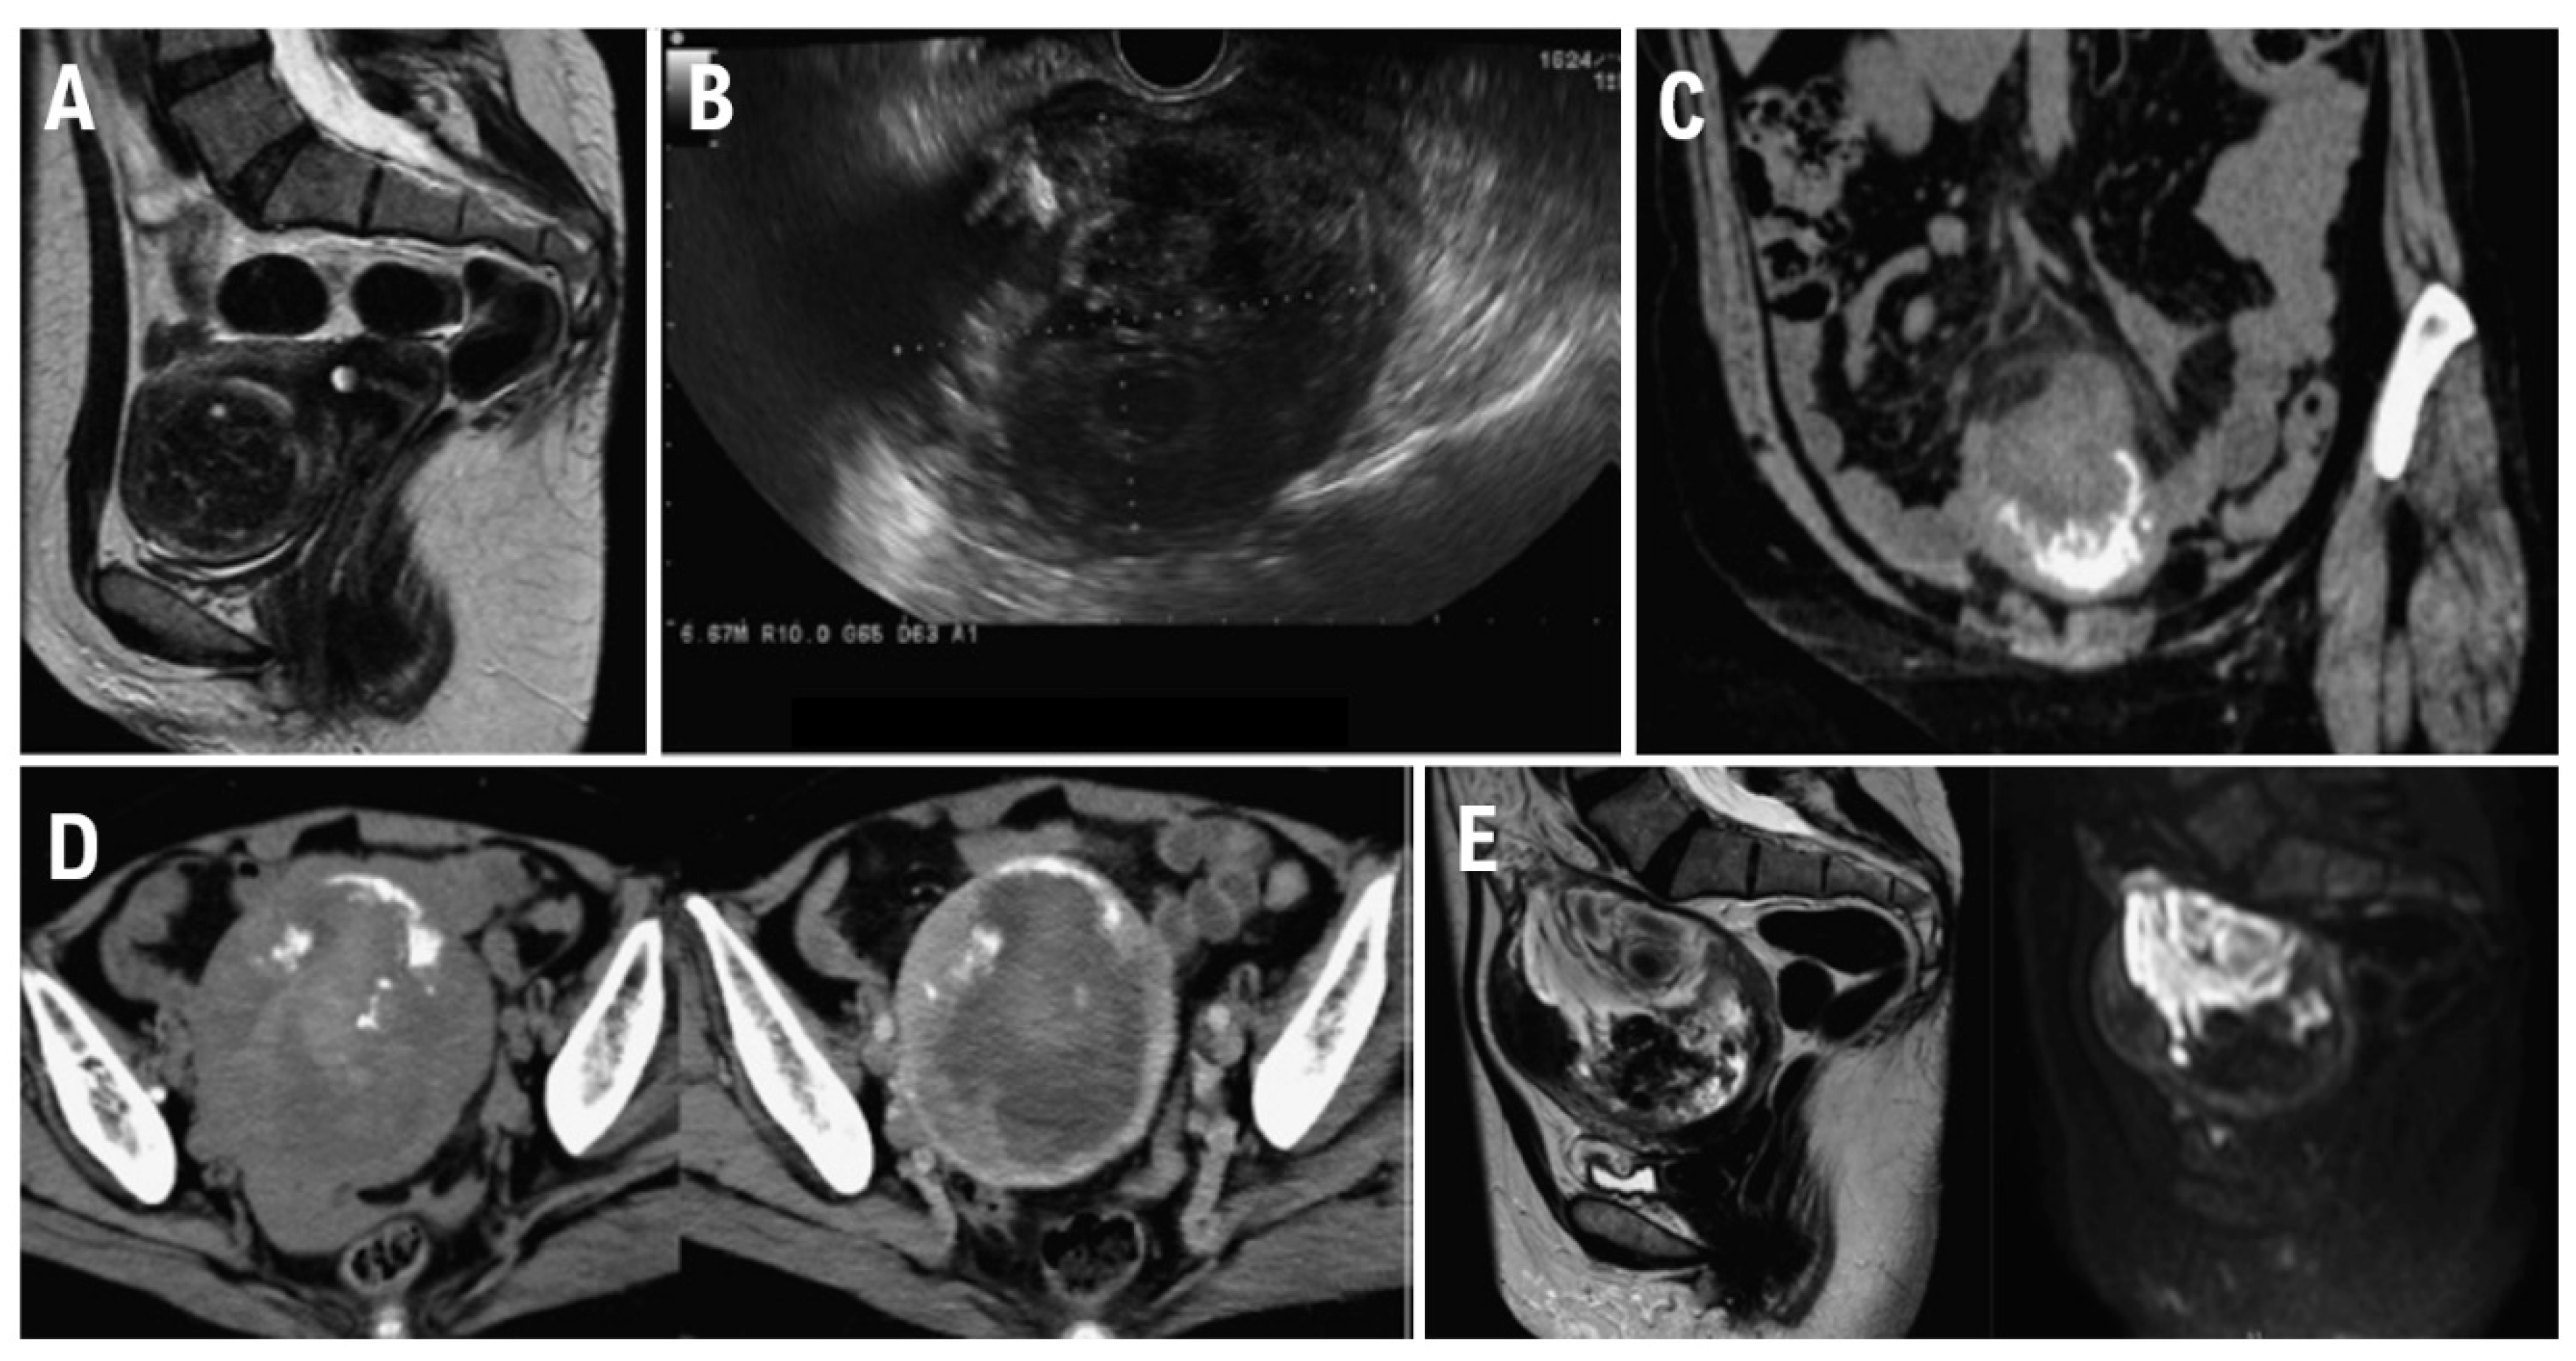

At 48 years of age, the patient was diagnosed with anemia (Hb 8.8 g/dL). She was therefore referred to our gynecological clinic for further evaluation to determine whether a gynecological disease was present. Transvaginal ultrasonography revealed a large 48 mm × 50 mm mass compressing the lining of the anterior uterine wall. Based on contrast-enhanced magnetic resonance imaging (MRI) findings, the mass was diagnosed as a uterine leiomyoma (Figure 1A). However, because the patient preferred monitoring until menopause, we prescribed iron supplements to treat the anemia and continued tumor follow-up. The tumor did not show any signs of enlargement. At 56 years of age, however, she developed lower abdominal pain after undergoing an endoscopic examination of the lower gastrointestinal tract. Blood test results revealed an elevated C-reactive protein (CRP) level of 8.49 mg/dL. We suspected the development of peritonitis due to delayed perforation and therefore performed contrast-enhanced CT. The imaging showed increased adipose tissue density in the mesenteric lining around the uterus as well as ascites.

Transvaginal ultrasonography showed a 90 mm x 69 mm heterogeneous mass with irregular margins in the uterine body (Figure 1B).

Truncal computed tomography (CT) (Figure 1C) revealed a 10 cm x 11 cm mass with marginal calcification on the anterior uterine wall and cranial protrusions of the uterus. A pale, low-density area suggestive of hemorrhage was observed within the mass, and a small amount of pelvic fluid was present, suggesting the presence of blood. Increased adipose tissue density surrounding the mass suggested possible rupture.

A contrast-enhanced CT performed for preoperative evaluation 8 days after the initial scan showed that the uterine mass had decreased to 9.5 cm × 9.5 cm and the bloody ascites had resolved (Figure 1D). The fat density surrounding the cranial protrusion of the uterus had decreased, and the wall in that region had thinned. The low-density background area within the mass had become less prominent, suggesting a reduction in bloody fluid. No lymph node enlargement or distant metastasis was observed.

Pelvic contrast-enhanced MRI (Figure 1E) showed a 10 cm mass located within the muscle layer of the anterior uterine wall. T2W1 demonstrated moderate signal intensity within the mass, and DWI demonstrated high signal intensity. Heterogeneous internal signals suggestive of hemorrhage and necrosis were present. T2W1 also showed signal imaging, which showed a low-signal area on the ventral side of the mass. CT demonstrated areas of calcification, and contrast-enhanced MRI confirmed that both ovaries were normal.

Figure 1. A. MRI performed at the initial consultation. The mass exhibited a clearly demarcated low signal intensity on T2W1 and was diagnosed as a uterine fibroid. B. Transvaginal ultrasound after lower gastrointestinal endoscopy revealed a 90 x 69 mm mass in the uterine body, with a heterogeneous interior and irregular margins. C. Plain CT: Increased density was observed in the mesenteric fat tissue surrounding the mass. A mass with marginal calcification was found on the anterior wall of the uterine body, protruding cephalad. D. Comparison of the initial CT (left) with a CT performed 8 days later for preoperative evaluation (right). The uterine mass had shrunk from 10 x 11 cm to 10 x 9.5 cm, and the absorption value of the internal high-density area had decreased, suggesting absorption of the hematoma. E. MRI for further investigation of suspected uterine sarcoma. The mass showed moderate signal intensity on T2W1 and high signal intensity on DWI, and heterogeneous signals were present within it, suggesting hemorrhage and necrosis.